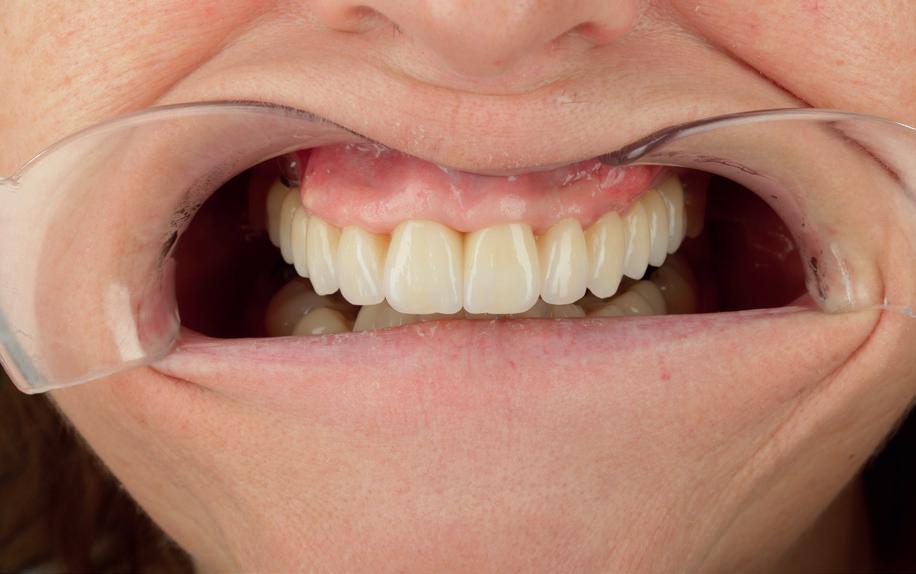

Esthetiek in de tandheelkunde, met name in het front, is een samenspel tussen de roze zachte weefsels en de witte harde weefsels. In het Engels wordt dit ook wel aangeduid met “pink and white esthetics”, waarbij het verkrijgen van correcte pink esthetics over het algemeen een grotere uitdaging vormt dan de white esthetics. Deze roze esthetiek is vooral van belang bij gebitselementen waarbij sprake is van recessie (het terugtrekken van de gingivalijn, waardoor de radix en een langere tand zichtbaar worden). De situatie wordt nog uitdagender wanneer een tand of kies niet is aangelegd, of in het verleden is verwijderd. Het element zorgt er immers voor dat de gingiva rondom de natuurlijke kroon ligt en dat er voldoende weefseldikte rondom deze kroon aanwezig is. Als het element ontbreekt, groeit het alveolaire bot dicht, omdat er geen radix meer is, en daarmee ook de mucosa (wanneer er geen element meer aanwezig is, spreken we niet meer van gingiva maar van mucosa), die dan afgevlakt is. De papillen tussen de afwezige elementen vlakken dan ook af.

Om één of meer afwezige elementen te herstellen bij een vaste voorziening, kan er een etsbrug of kunnen er implantaten worden geplaatst. De esthetiek valt of staat hierbij met de aanvulling van de zachte weefsels, zowel in de vorm van verbreding hiervan als het creëren van een zogenoemd emergence profile –dat wil zeggen dat de tand op een natuurlijk ogende wijze vanuit het tandvlees tevoorschijn moet komen.

Op 16-jarige leeftijd werd de patiënt door haar behandelend orthodontist naar de auteur verwezen voor een restauratieve oplossing voor de afwezige 11 en 21. In de tussenliggende periode had patiënt een retainer gedragen met twee kunststof tanden (afbeelding 1). Zowel de patiënt als haar moeder hadden een sterke voorkeur voor een implantaat gedragen vaste oplossing. Gezien haar jonge leeftijd was dit echter nog geen optie, omdat er nog verticale groei te verwachten viel. Implanteren op jonge leeftijd – dat wil zeggen vóór het 21e levensjaar – kan resulteren in een infrapositie van het implantaat, omdat de rest van het gebit nog verticaal kan doorgroeien.

Middels shared decision making werd het volgende plan overeengekomen: eerst zou er een etsbrug met vleugels op de 12 en 22 worden vervaardigd, om op 21-jarige leeftijd verder te gaan met implantologie.

van de patiënt, om eerst weer vaste apparatuur terug te plaatsen om de radices in een divergerende stand te plaatsen. Gelukkig verliep deze behandeling voorspoedig. (afbeelding 2 -4). Het volgende behandelplan werd gemaakt:

• Intra-orale scan voor studiemodellen, proefopstelling en beoordelen ruimte palatinaal

Vervaardigen essix retainer met dummies waarbij er een emergence profile van de 11 en 21 werd gevormd door eivormige dummies 4 mm in de gingiva te plaatsen

• Aanvulling zachte weefsels met de VISTA techniek en een vrij gingivatransplantaat uit het palatum links en direct dragen van de essix retainer

Na 4 weken intra-orale scan voor de etsbrug en kleurbepaling bij de technicus

• Plaatsen van de etsbrug met een composietcement

Voordat er gescand kon worden voor een etsbrug, werd een studiemodel vervaardigd om met de technicus te overleggen of er voldoende ruimte was voor 2 centrale incisieven in de mesio-distale zin en of er voldoende ruimte was in occlusie voor de vleugels van de etsbrug. Er hoeft enkel nog aan de 12 en 22 pala-

tinaal geslepen te worden als er geen 1,5 mm ruimte voor de vleugels behaald kan worden. De ruimte was op de dunste plekken 1 mm, dus een kleine preparatie in de 12 en 22 palatinaal was nodig. Omdat de kaak volledig afgevlakt was en dun was geworden, kunnen de dummies van de etsbrug enkel op de kaak “gelegd worden”, maar daarbij zijn er geen papillen en staat de cervicale rand van de dummies net voor de kaak. Een esthetisch resultaat kan daarmee niet behaald worden. Daarom is een aanvulling van de zachte weefsels in de breedte nodig, als het creëren van een emergence profile, waarbij het oogst alsof de gebitselementen uit het weefsel vertrekken.

18. Etsbrug frontbeeld

19. Etsbrug palatinaal